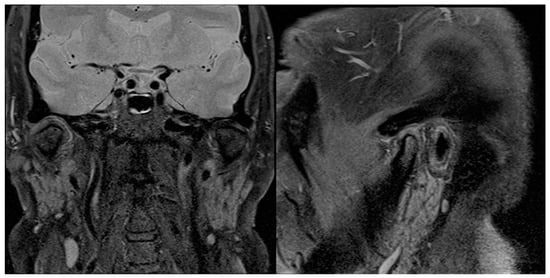

Between January 2016 and December 2022, 16 patients with clinical and radiological suspicion of SC underwent diagnostic and operative TMJ arthroscopy. Preoperative and postoperative clinical and imaging data (Figure 9) were recorded and are shown in Table 3. Physical examination data at the 6-month follow-up evaluation were analysed to better match the imaging data collected from the 6-month postoperative MRI (Figure 10). Patient age ranged from 24 to 72 years, with a mean of 50.9 years. A sex predominance was observed, with 13 female (81.2%) and just 3 male patients (18.8%). All case reported were monoarticular, with a small prevalence in affected joint of the left side (62.5%) compared to the right side (37.5%). Physical examination records showed a preoperative MIO ranging from 20 to 38 mm with a median of 29.6 mm, while the postoperative MIO ranged from 25 to 48 with a median of 37.9 mm, showing an 8 mm MIO improvement after surgery (Figure 11). Pain assessed with VAS showed a significant improvement of almost 5 units, with the preoperative values ranging from 6 to 8 with a median of 7.1 and the VAS assessed six months after surgery ranging from 0 to 7 with a median of 2.6. All 16 patients were submitted to an MRI before the surgery, while a CT scan was performed in just five patients. The diagnosis of SC was confirmed by histopathological examination and classified following Milgram classification: six patients (37.5%) were classified as a stage 1, as many as the ones classified as stage 2, while four patients (25%) were classified as stage 3. There were no extracapsular soft-tissue involvements that were proven by pathology and MRI in all subjects. It was not possible from the data collected to determine with certainty which form of SC, primary or secondary, the patients were suffering from. The follow-up period ranged from 8 to 71, months with a mean value of 30.6 months. Only 2 of the 16 patients (12.5%) showed a recurrence of SC, and in both cases, this was noticed at the 6-month follow-up evaluation. These two patients were then submitted to open surgery within 6 months of the relapse diagnosis. One of these two patients needed a second arthrotomy 18 months after the first one, because another relapse of SC was noticed at the follow-up MRI.

Figure 9.

Preoperative sagittal and coronal MRI scans showing, on the right, TMJ joint effusion and LBs, but no bony involvement.

Figure 10.

The 6-month postoperative sagittal and coronal MRI scans showing no signs of relapse on the right TMJ.